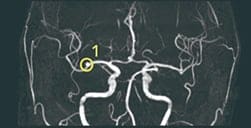

(例) MRA画像から脳動脈瘤の候補点を検出するアルゴリズムの組み合わせ

脳動脈瘤の

候補を検出